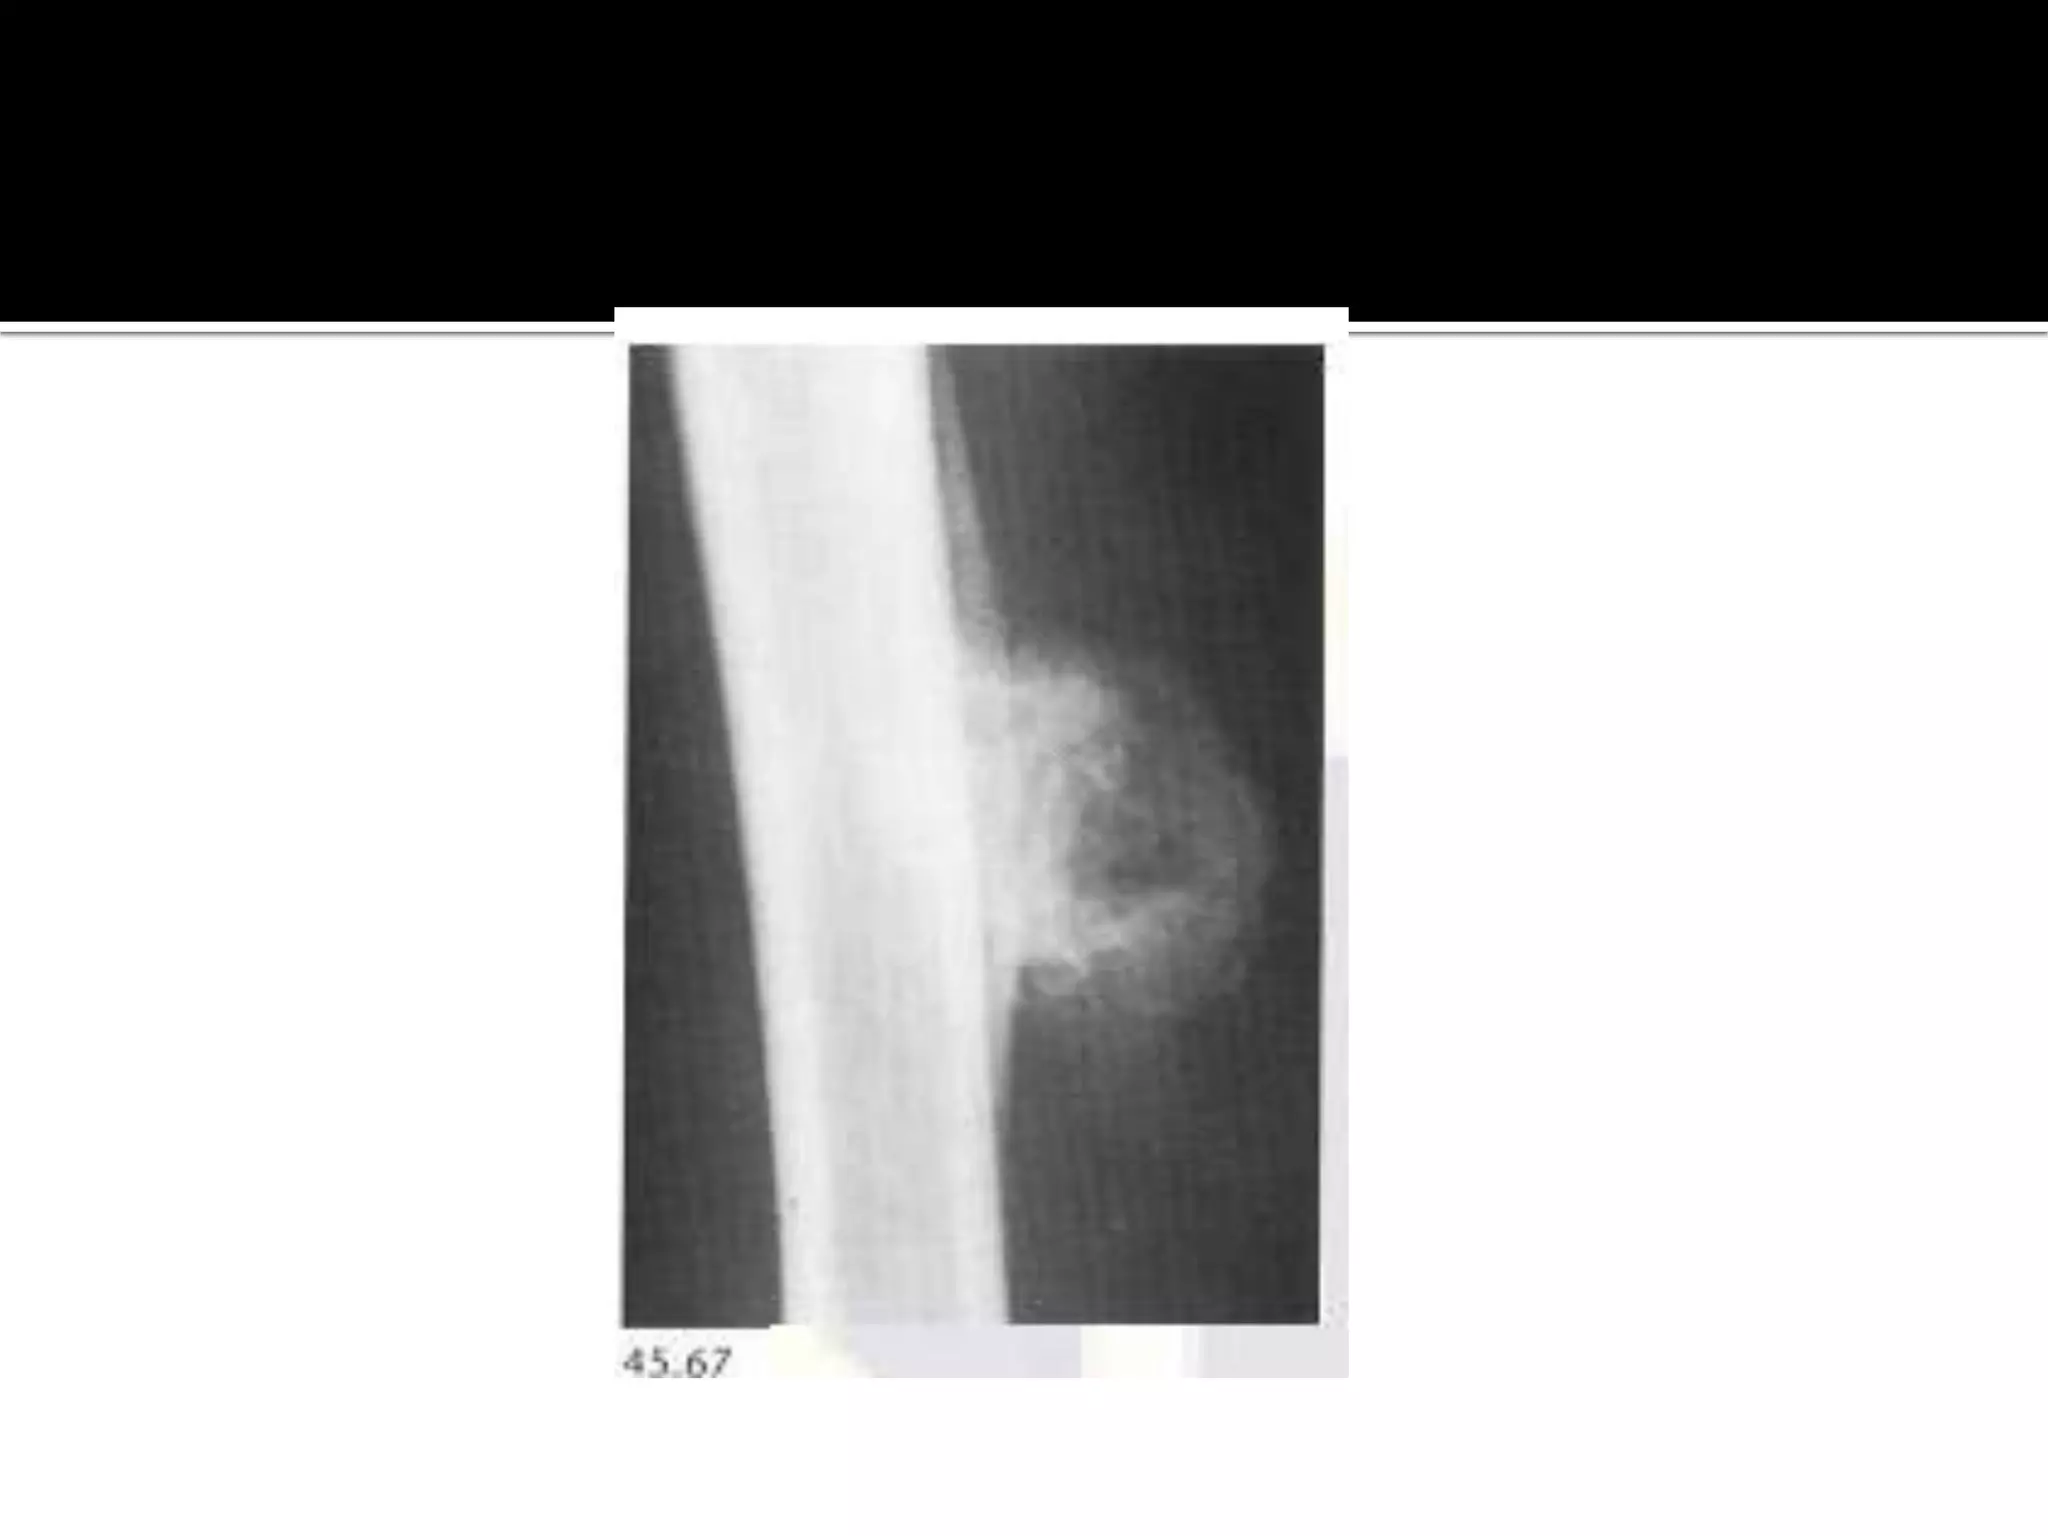

Post-traumatic myositis

 it results in a soft tissue mass which ossifies with a lacy

pattern by 4-8 weeks.

 common sites are the elbow and knee.The ossification

may resolves.

• 45.

Post-traumatic myositis  itresults in a soft tissue mass which ossifies with a lacy pattern by 4-8 weeks.  common sites are the elbow and knee.The ossification may resolves. Paraplegic myocitis ossificans.  it develops in paraplegics within 3-4 weeks below the level of the paralysis.There is hetrotopic periarticular calcification and ossification around the joints particularly the hip with irregular plaques of bone forming.